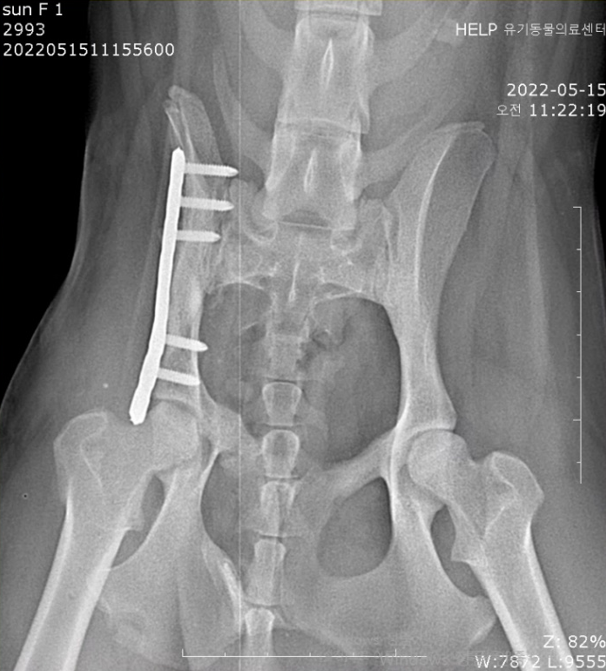

Çüµé! ¿À´ÃÀº '¸Û¼øÀÌ'¶ó´Â °¾ÆÁö¸¦ ¼Ò°³ÇÏ·Á°í ÇØ~! ¸Û¼øÀÌ´Â °³³óÀå ¶áÀå¿¡¼ Å»ÃâÇÑ ¾ÆÀ̾ß. ±ØÀûÀ¸·Î Å»Ãâ ÈÄ ÀÎõ °è¾ç±¸ ÁÖÀ§¸¦ µ¹¾Æ´Ù´Ï´Ù°¡ ±³Åë»ç°í¸¦ ´çÇß´Ù°í ÇÏ´õ¶ó±¸. £¨±×¶§±îÁö ½ÃÀå »óÀÎ ºÐµé¿¡°Ô ¸ÔÀ» °É ¾ò¾î¸ÔÀ¸¸é¼ Áö³Â´Ù°í ÇØ¤Ì¤Ì£© ÀÌÈÄ À¯±â°ß ¼¾ÅÍ¿¡ ÀÔ¼Ò ÈÄ, Áö³ 4¿ù 8ÀÏ ±¸Á¶µÇ¾ú¾î. ±×¸®°í Áö³ 4¿ù 17ÀÏ º´¿ø¿¡ ³»¿øÇØÁÖ¼ÌÂî! ³»¿ø ´ç½Ã ¾ÆÀÌÀÇ »óÅ´ ÀÌ·¯Çß¾î. - ¿ìÃø °ñ¹Ý»ÀÀÇ Àå°ñ³¯°³£¨iliac wing£© °ñÀý - °ñÀýµÈ Áö 1´Þ ÀÌ»ó µÇ¾úÀ¸¸ç, - À§ »çÁø¿¡¼ º¸½Ã´Â °Íó·³, ÃÊ·Ï»öÀ¸·Î Ç¥½ÃÇÑ 1¹øÀÌ È»ìÇ¥ ³¡ºÎºÐ¿¡ ¿¬°áµÇ¾î ÀÖ¾î¾ß ÇØ. - ÇÏÁö¸¸ °ñÀýµÈ Áö ¿À·¡µÇ¾î, ¾ûµ¢ÀÌ ±ÙÀ°ÀÇ À§Ãࣨadaptive shorteningÀÌ ¿¹»óµÇ¾ú¾î£© - ºÎ·¯Áø °ñ¹Ý»À°¡ ±²ÀåÈ÷ °ñ¹Ý ¾ÈÂÊÀ¸·Î µé¾î°¡ ÀÖ°í, - ±ÙÀ°ÀÌ Âª¾ÆÁ® ºÎ·¯Áø »À°¡ ¸Ó¸® ¹æÇâÀ¸·Î ¿Ã¶ó¿Í ÀÖ¾úÁö. µû¶ó¼ ¼ö¼úÀº ÀÌ·¸°Ô ÁøÇàµÇ¾ú¾î. - µÞ´Ù¸® ±ÙÀ° ¹× ¾ûµ¢ÀÌ ±ÙÀ°À» ÀÚ¸£°í Á¥Çô°¡¸ç °ñÀýµÈ ºÎÀ§¿¡ Á¢±ÙÇß°í, - ³»ÃøÀ¸·Î º¯À§µÈ Àå°ñ ³¯°³¸¦ ¹Ù±ùÀ¸·Î ²¨³½ ÈÄ ¿ø·¡ À§Ä¡¿¡ ¸ÂÃçÁÖ¾ú¾î. - °ñÀýµÈ Áö ¿À·¡µÇ¾î, ºÎ·¯Áø »À¿¡ ºÙÀº ±ÙÀ°ÀÌ ½ÉÇÏ°Ô º¯ÇüµÇ¾î ÀÖ¾ú¾î. - µû¶ó¼ ºÎ·¯Áø »À¸¦ ¿ø·¡ À§Ä¡¿¡ ¸ÂÃß´Â µ¥¸¸ 2½Ã°£ ÀÌ»óÀÌ ¼Ò¿äµÇ¾ú¾î. ¼ö¼úÀº ¸Å¿ì Àß µÇ¾úÀ¸¸ç, - ¼ö¼ú ÈÄ¿¡´Â 1ÁÖÀϰ£ ÀÔ¿øÀå »ýȰÀ» Çß¾î. - Åð¿ø ÈÄ 4ÁÖ°£Àº ½Ç³» ÀÚÀ¯ »ýȰÀ» Çϸç, - 2~4ÁÖ¿¡ ÇÑ ¹ø¾¿ X-ray ÃÔ¿µÇÒ ¿¹Á¤À̾ß. - ¿À¸¥ÂÊ ´Ù¸®ÀÇ ¿îµ¿¼º ¹× ¹èº¯Àº Á¤»óÀûÀ¸·Î ÇÏ´ÂÁö ¸ð´ÏÅ͸µÇÒ ¿¹Á¤À̰í! - ±×¸®°í Ç÷¹ÀÌÆ®ÀÇ ±æÀ̰¡ Á¶±Ý ±ä µíÇÏ¿©, 6°³¿ù µÚ Ç÷¹ÀÌÆ® Á¦°ÅÇÒ ¿¹Á¤ÀÌÁö! ±×¸®°í ÀÌ°Ç Åð¿ø Àü ÂïÀº »çÁø! ³Ñ Àß µóÁö!! ¿ì¸® ¸Û¼øÀÌ ³Ñ³Ñ ±âÆ¯ÇØ! ¤Ð¤Ð¤Ð ¸Û¼øÀÌ´Â »ç¶÷¿¡ ´ëÇÑ »óó°¡ ÀÖÀ» ÅÙµ¥µµ, ³Ê¹« ÂøÇØ¼ ´õ´õ¿í ¸¶À½ÀÌ ¾ÆÆÍ¾î ¤Ì¤Ì... Ä¡·á ÈÄ¿¡´Â ±¸Á¶ÀÚ´Ô ´ì¿¡¼ Áö³»¸é¼, ÀÔ¾ç º¸³¾ ¿¹Á¤À̶ó°í ÇØ! ¿ô´Â ¸ð½Àµµ ¿¹»Ú°í ÂøÇØ¼ ²À ÁÁÀº °¡Á·À» ¸¸³¯ °Å¾ß ¸Û¼ø¾Æ! ¸Û¼øÀÌ ³Ê¹«³Ê¹« »ç¶ûÇØ! ³Ê¹«³Ê¹« ±âƯÇϰí ÂøÇÑ ¸Û¼øÀÌ °í¸¶¿ö ¢½ ¢½ °¡Á·ÀÇ Ç°ÀÌ Àý½ÇÇÑ ¸Û¼øÀÌ¿¡°Ô ¸¹Àº °ü½É ºÎÅ¹ÇØ!!! À̸§: ¸Û¼ø £¨¿©¾Æ, Áß¼ºÈ ¿Ï·á£© ³ªÀÌ: 1¼¼ Ư±â: ÇØ¸¼Àº ¿ôÀ½¢¾